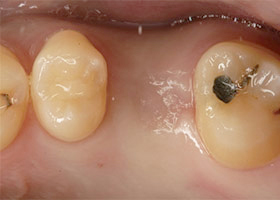

傳統植牙方式是屬於”手術行為”,病患需接受局部麻醉,再以劃開牙肉、翻瓣、鑽孔的將植體植入牙齦內的齒槽骨中。 這樣的手術方式,療程時間較長,且傷口較大,所產生的疼痛、出血腫脹以及傷口復原的時間也相對較長。